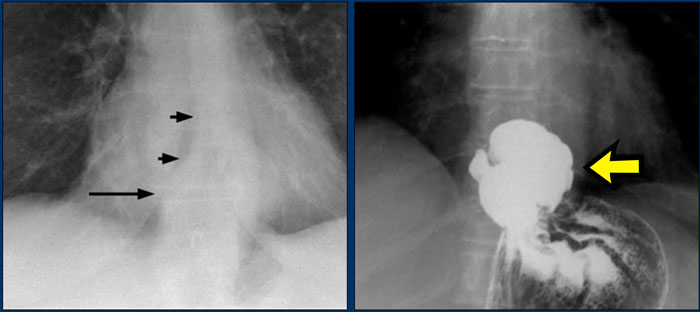

A key mediastinal–pulmonary interface to assess is the azygoesophageal recess (yellow arrow).

Azygo-esophageal recess

The azygoesophageal recess is located below the level of the azygos vein arch.

In this region, the medial aspect of the right lower lobe abuts the mediastinum between the heart anteriorly and the vertebral column posteriorly.

On its left, it is bordered by the esophagus.

Deviation of the azygoesophageal line may result from:

• Hiatal hernia

• Esophageal pathology

• Left atrial enlargement

• Subcarinal lymphadenopathy

• Bronchogenic cyst

On the PA chest radiograph, a lateral displacement of the azygoesophageal line can be seen.

It is caused by a hiatal hernia.

The arrow points to the barium contrast within the hiatal hernia.

Displacement of the Azygoesophageal Line (1) – Hiatal hernia

A hiatal hernia (arrowheads) is the most common cause of displacement of the azygoesophageal line as seen on the PA-view.

Notice the air within the hernia on the lateral view (black arrow).